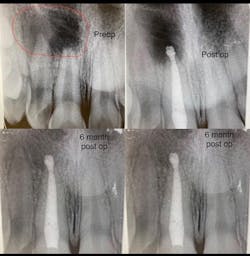

- The type of endodontic treatment dictates the length of healing. Nonsurgical endodontic treatment has a usual healing time of three months. Surgical intervention such as an apicoectomy due to large lesion size can take six to 12 months to heal (figures 1 and 2).